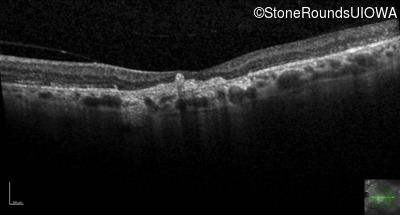

Infrared Fundus Photograph - Right - 20/80

Exemplar